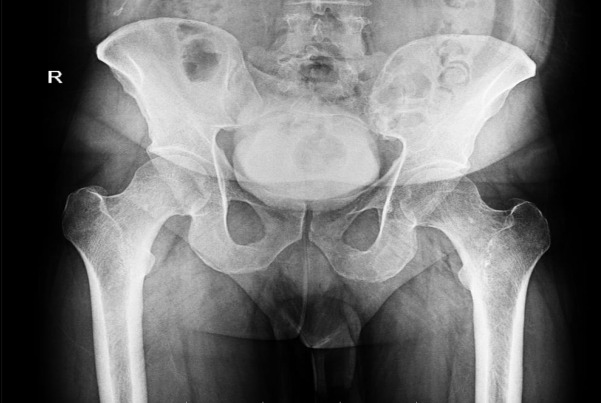

31 cases of fibromatosis were found in our database, which has data on over 10,000 patients, including those with benign bone tumours. Of these patients, 4 had desmoplastic fibroma of the bone, meaning that the incidence of fibromatosis in our population was 0.04%. Out of which three (75%) were men and one (25%) was a woman. The average age was 29.25 years (range: 21–35 years old). The skeletal distribution was one scapula, two pelvises, and one chest wall- rib. Fig-1.